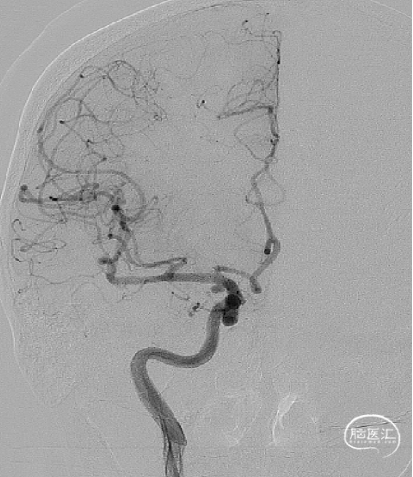

右侧颈内动脉造影:

左侧颈内动脉末端夹层动脉瘤、左侧大脑中动脉分叉部动脉瘤、右侧颈内动脉脉络膜前动脉处动脉瘤。

a.左侧颈内动脉末端夹层动脉瘤形状不规则且囊体较大,大脑中分叉部动脉瘤有一分支发出,这两处动脉瘤相对危险性高,此次优先处理;右侧脉前动脉瘤二期治疗。